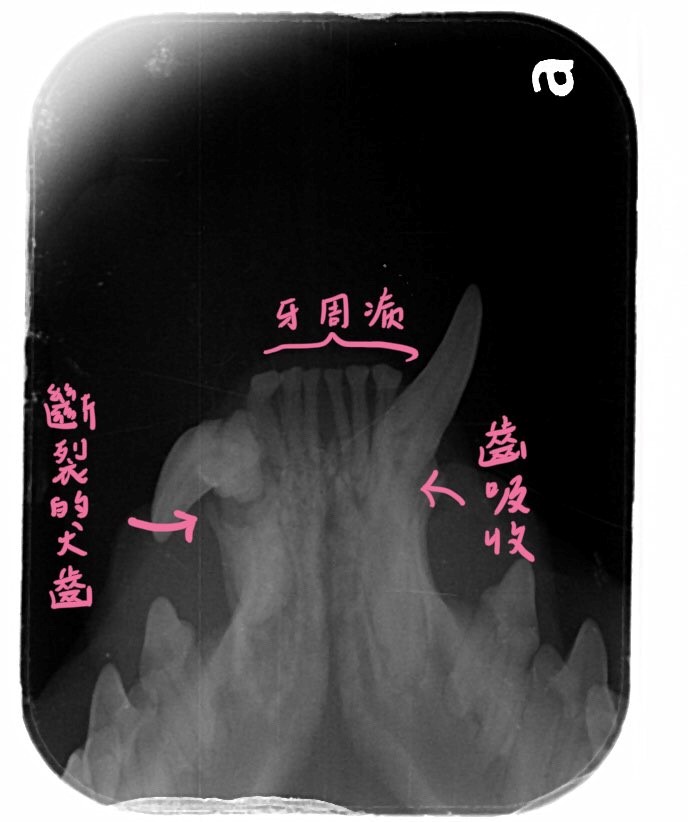

麻醉下評估

麻醉下檢查發現歪掉的牙齒牙冠都斷裂且牙髓已暴露感染才會造成牙齦腫脹

本來以為最正常的左下犬齒也有齒吸收的問題

將這些發育異常且已感染的牙齒移除